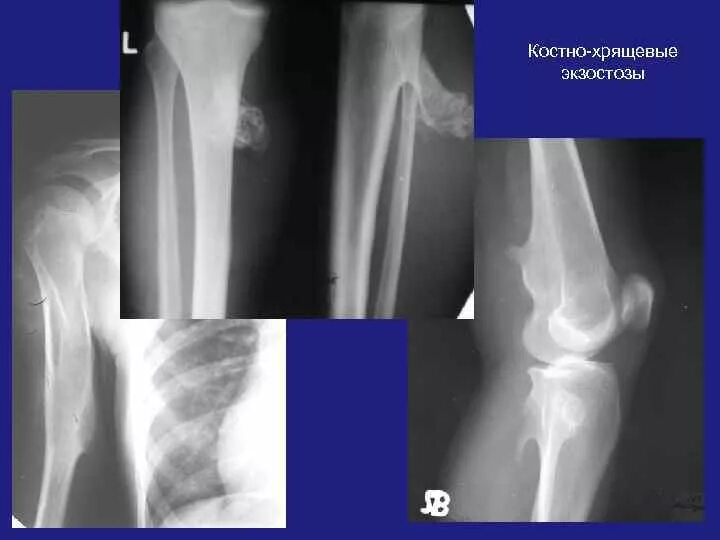

Экзостоз мкб 10